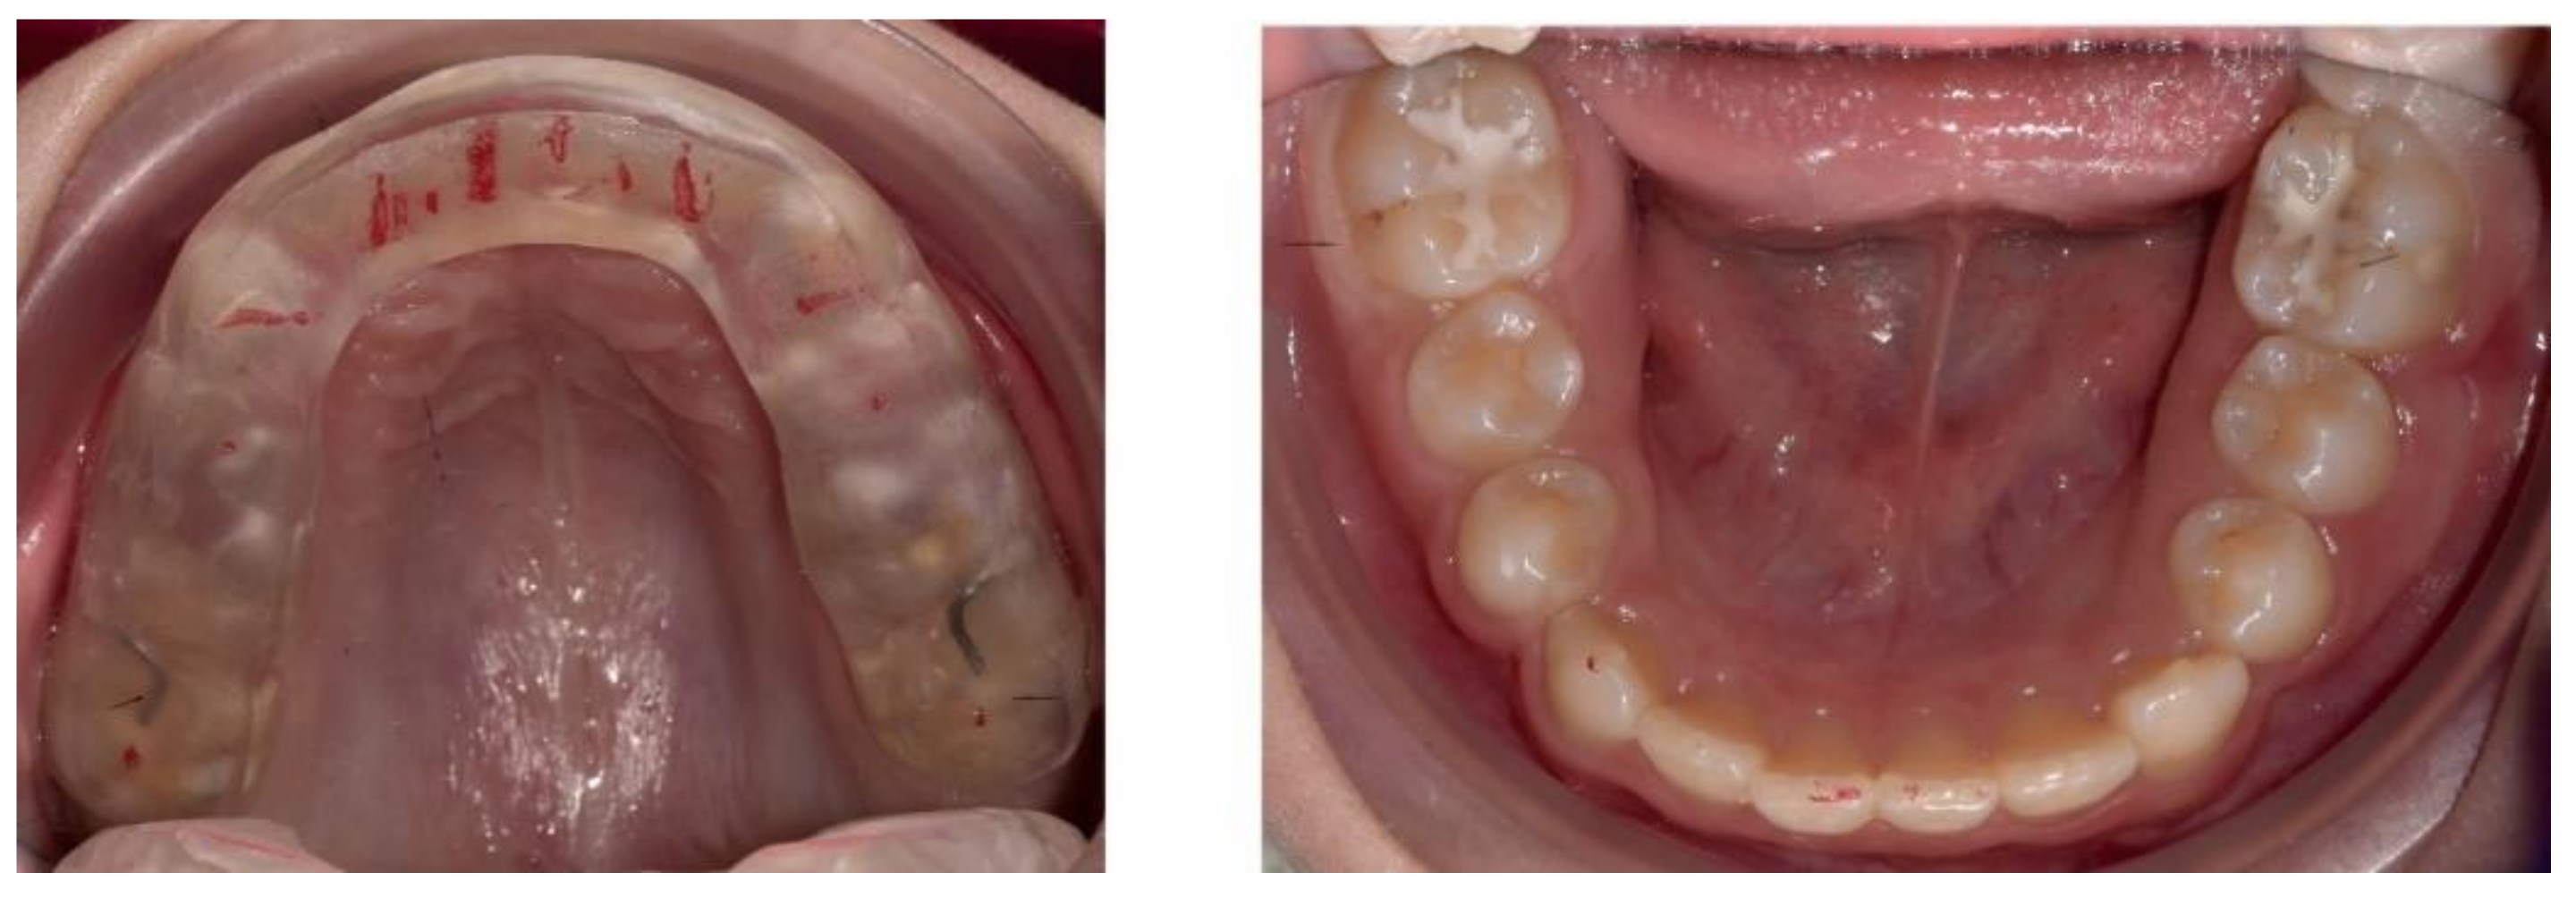

2.3.2. Second Phase of Treatment—2017—Bite-Blocks and Transpalatal Arch